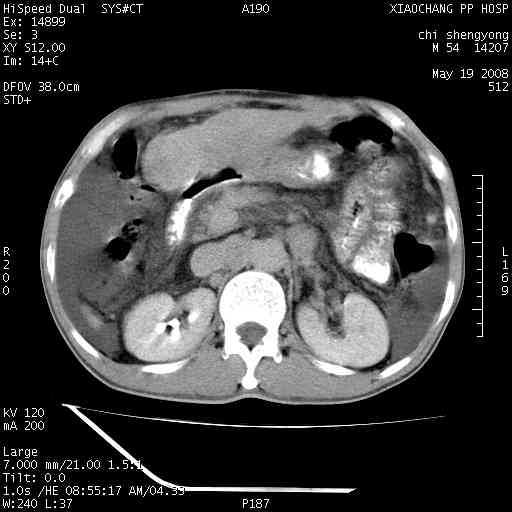

以下是引用zjzjr在2008-5-21 10:52:00的发言:[br]肝左叶巨块型肝癌伴门静脉左支瘤栓形成.肝硬化、腹水,胃底静脉曲张,脾术后改变。

以下是引用随光逐影在2008-5-21 16:20:00的发言:[br]1)肝左叶肝癌伴门静脉左支瘤栓形成,腹膜后淋巴结转移。2)肝硬化、腹水、胃底静脉曲张。3)胆囊炎。4)脾脏缺如,为切除术后所致。